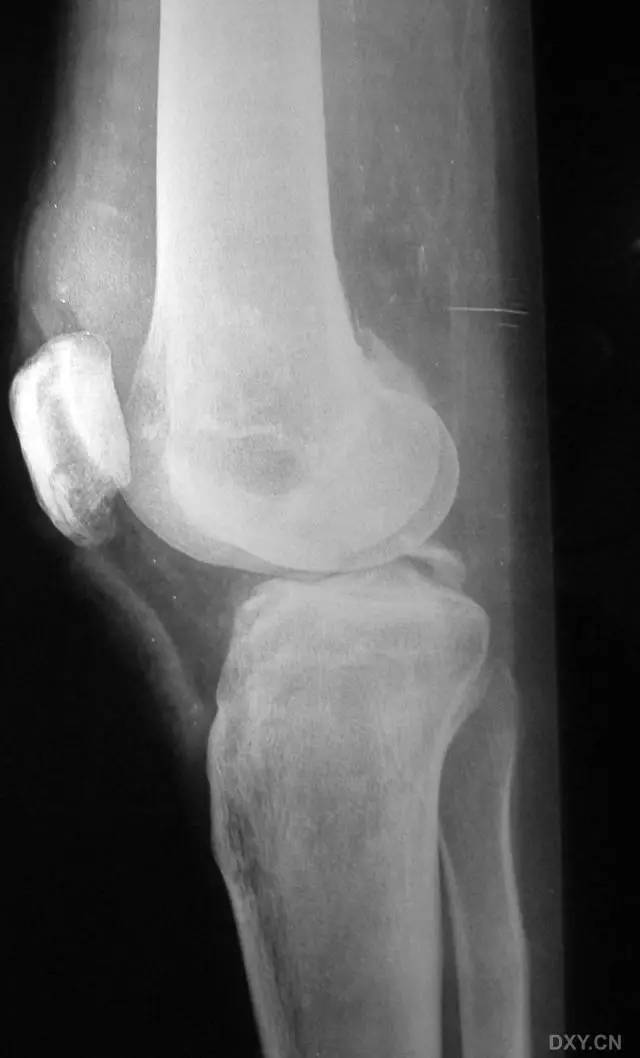

8. Segond 骨折和反向 Segond 骨折

(1)Segond 骨折

是发生在胫骨平台外侧的垂直撕脱性骨折。这种骨折在前后位 X 线片上显示最佳。屈曲位时膝关节受到内旋暴力作用,导致皮质骨撕脱性骨折,这种骨折常发生在运动员身上。

常引起股骨内髁和胫骨平台后内侧骨挫伤,75%~100% 的患者伴前交叉韧带断裂,33% 的患者伴外侧半月板损伤。

一位足球运动员的 Segond 骨折。A 正位片示关节线下方胫骨外侧皮质撕脱(箭头)。B MRI 冠状位 T1 加权像示附着于髂胫带的骨折碎片(空箭头)(来源:Radiol Clin N Am 53 (2015) 737–755,YU,Ohio)

(2)反向 Segond 骨折

胫骨平台内侧皮质骨撕脱性骨折,被称为内侧 Segond 骨折或反向 Segond 骨折。这种骨折的旋转机制与 Segond 骨折相反,该骨折与后交叉韧带断裂及内侧半月板损伤相关。

一位足球运动员的反向 Segond 骨折。A 正位片示关节线处的胫骨内侧见一细小骨折片(箭头)。B MRI 冠状位 T1 加权像示骨折片出现在内侧副韧带关节囊附着处(方框)(来源:Radiol Clin N Am 53 (2015) 737–755,YU,Ohio)